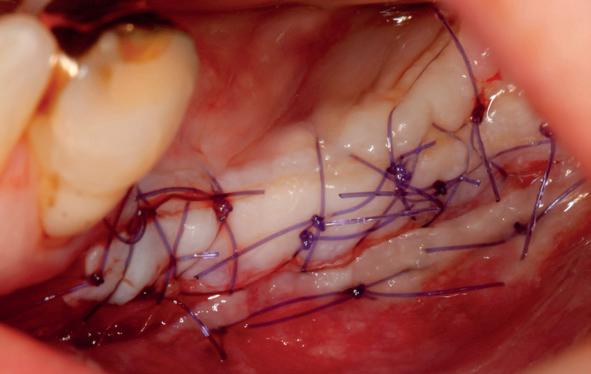

pincisies met hechtingen naar het buccale en coronale deel getrokken en aldaar ingehecht. Met twee incisies werd ook de emergence profile gecreëerd (afbeelding 6-13). Voor een goede genezing van het

11. Middels hechtingen het op de juiste plek trekken van het transplantaat

12. Transplantaat ingehecht

13. Occlusaal beeld verdikking van de zachte weefsels